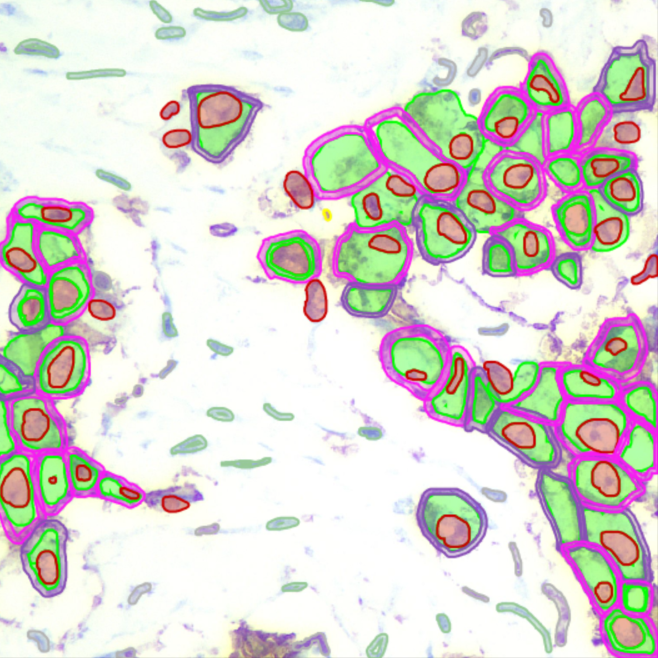

Biomarker Analysis

IHC scoring (Ki-67, PD-L1), ISH/FISH spot counting, and H-Score calculation for drug efficacy studies.